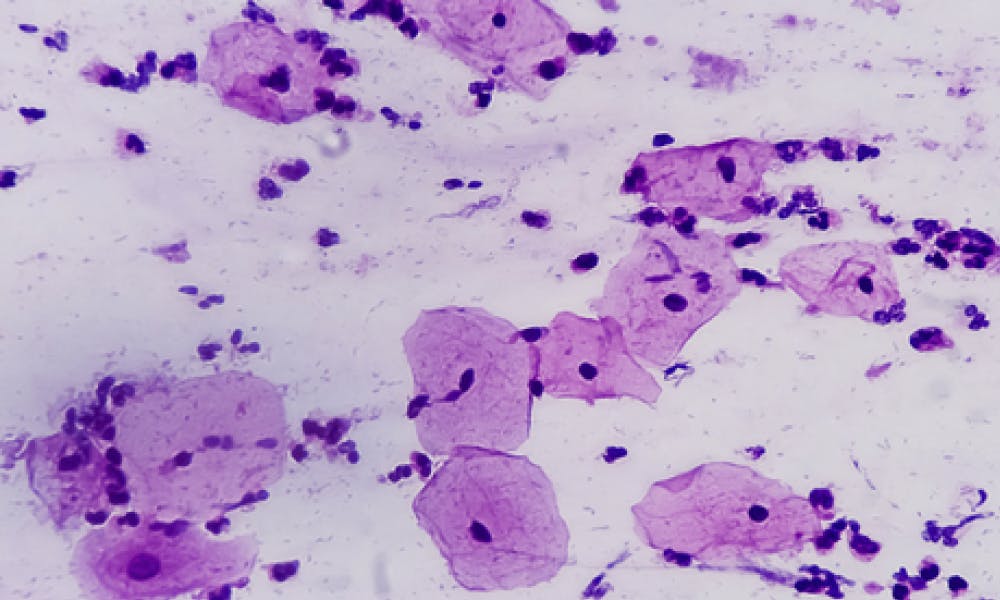

Preventing cervical cancer

WoW helped prove the link between HPV and cervical cancer, paving the way for national screening and vaccination programmes that cut rates by 63%.

A breakthrough in endometriosis care

Wellbeing of Women is currently funding a first-of-its-kind study developing a non-hormonal treatment that could safely shrink endometriosis lesions and ease pain — offering new hope to millions affected worldwide.